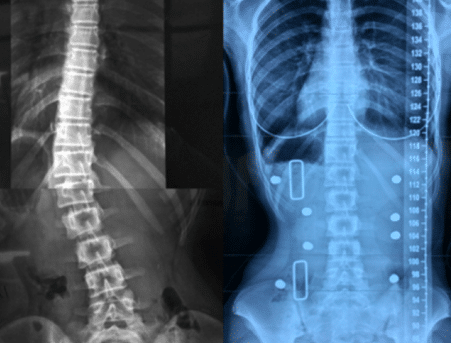

التنبؤ بنتائج حزام اعوجاج العمود الفقري :الفرق بين الأشعة داخل الحزام وخارجه…

التنبؤ بنتائج حزام اعوجاج العمود الفقري :الفرق بين الأشعة داخل الحزام وخارجه يُعد اعوجاج العمود الفقري عند المراهقين من أكثر حالات التشوهات الشائعة خلال مرحلة النمو، ويُعرف طبيًا باسم “الجنف مجهول السبب عند المراهقين”.